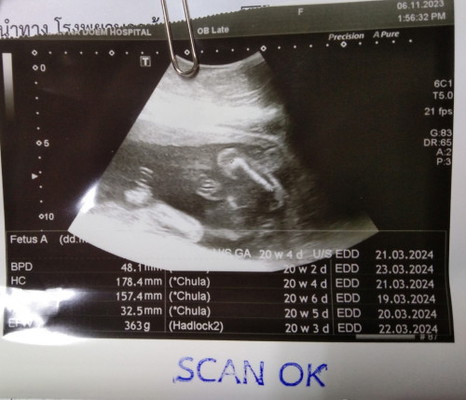

แม่ๆดูออกมั้ยคะว่าเพศอะไร

คุณหมอบอกว่าผู้ชาย ถ้าไม่มีอะไรผิดพลาดค่ะ

ผู้ชายค่ะแม่ เหมือนเห็นก้อนกลมๆระหว่างขา

ดูตรงระหว่างท่อนขาค่ะ ไม่แน่ใจนะคะแม่ ใช้จินตนาการล้วนๆ😅